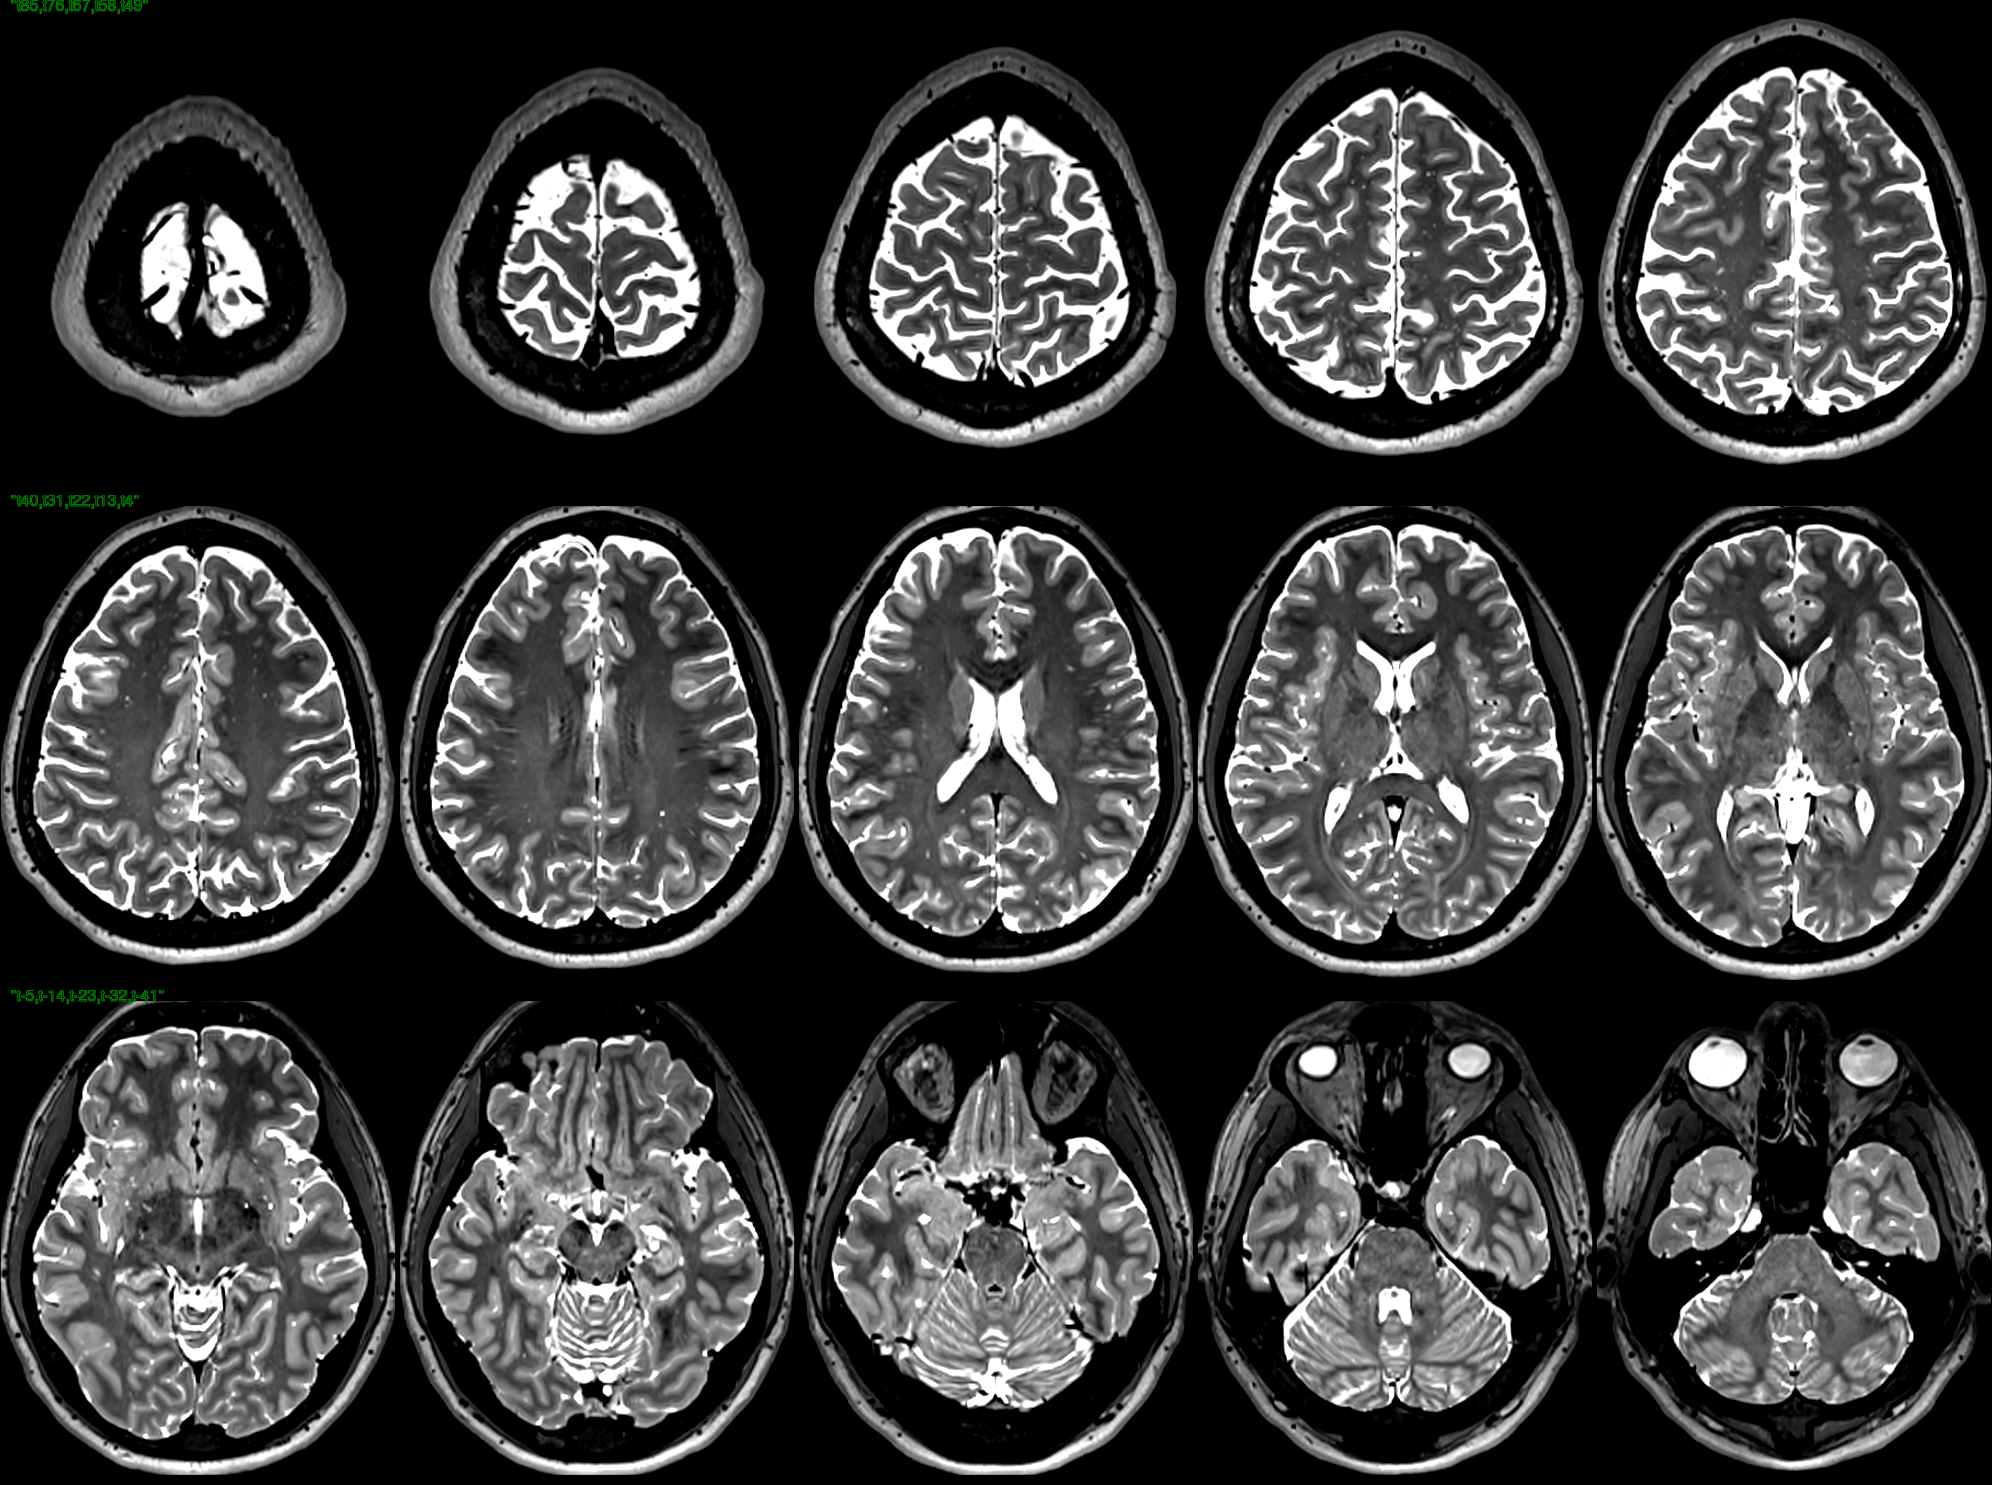

T2 images